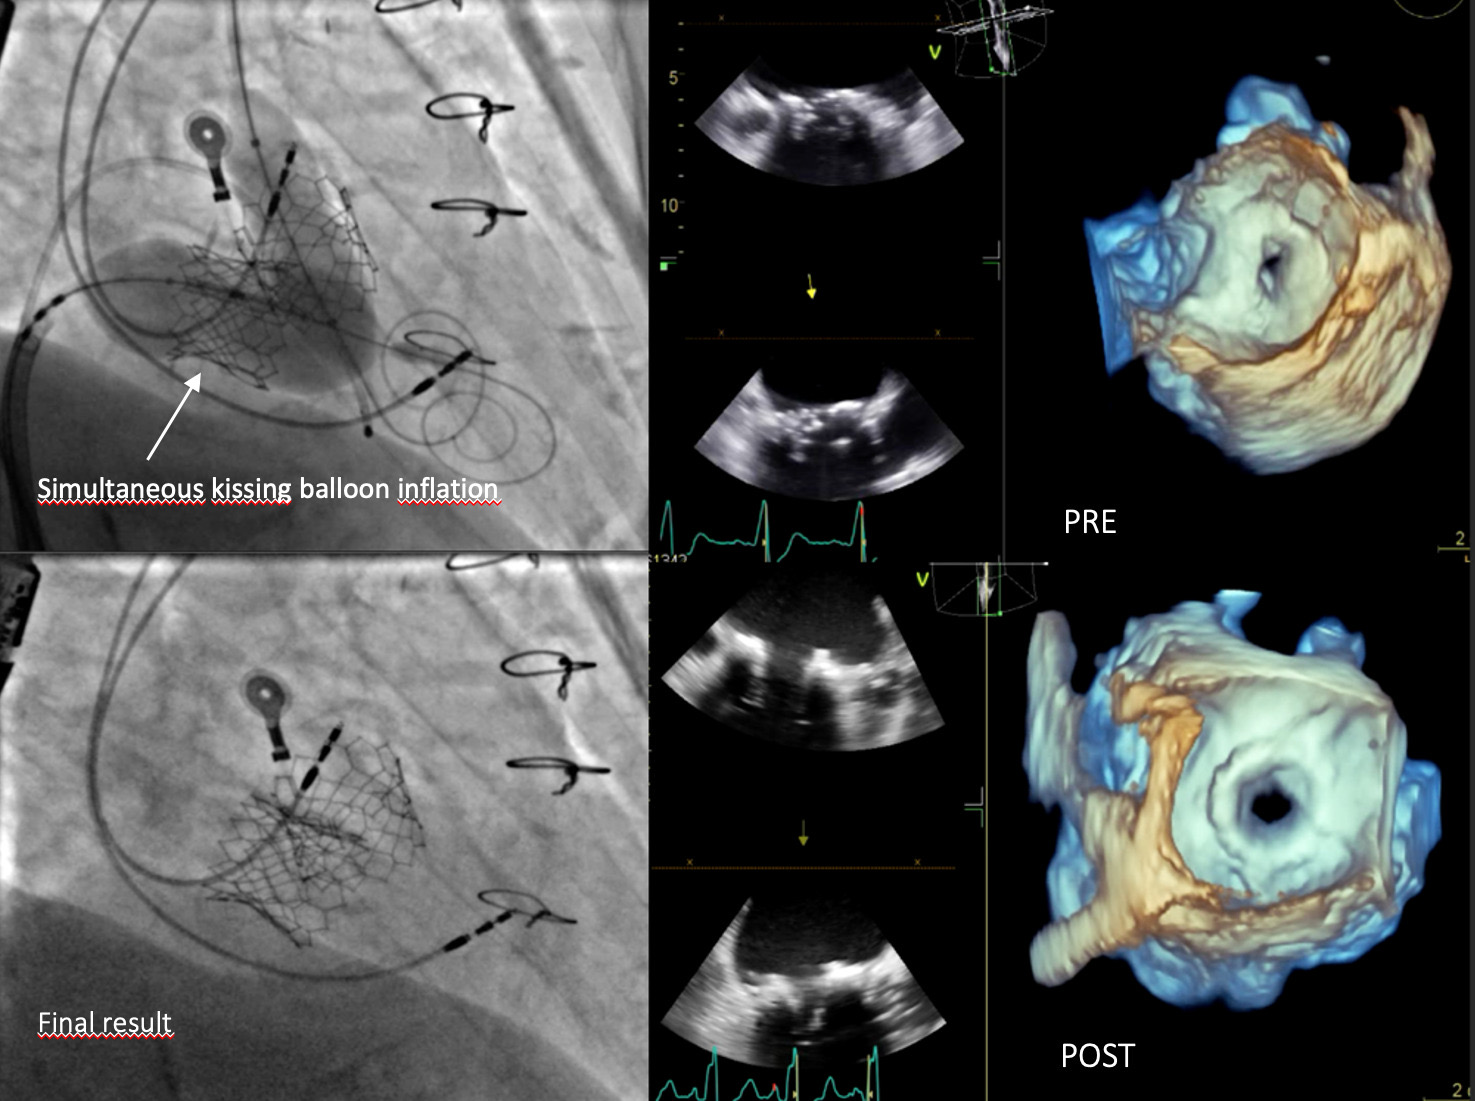

BACKGROUND Transcatheter mitral valve-in-valve implantation (TMVIV) into failing surgical bioprosthetic valves has evolved in recent years as a promising therapy to avoid redo cardiac surgery in patients at high surgical risk. METHODS An 80-year-old female patient with CKD stage 3, hypertension, a permanent PMK and atrial fibrillation was referred to our institution with NYHA Class III symptoms. She has undergone implantation of a bioprosthetic valve (St Jude Epic 29 mm) for severe mitral insufficiency due to chordal rupture in 2017 and transcatheter aortic valve implantation (Edwards 29 mm) for severe aortic insufficiency in 2022. The patient presented with structural valve degeneration, defined as intrinsic permanent variations of the tissue components of the valve, culminating in the development of severe intra-prosthetic stenosis. Notably her echocardiogram showed LVEF 45% with severe mitral valve deterioration due to calcification (mean gradient 15 mmHg, 3D MVA 0.8 cm^2). TAVI was normally functioning. Surgical risk for redo procedure was too high after evaluation by our Heart Team (EuroScore II 23,6%, STS Score operative mortality 16,7%). So, we have decided for a TMVIV using Edwards SAPIEN 3 Resilia valve 29 mm, implanted reversely in mitral position. The pre-procedural assessment for the "sizing" of the valve was performed using computed tomography angiography (CT). The following parameters were evaluated: the mitral annulus area, the aorto-mitral angle, the inverse angle and the distance between the two valves for evaluation of the neo-LVOT. The area of the mitral annulus was 6.2 cm² and thus suitable for a Sapien 3-29 mm. During procedure, angiographic imaging, but no TEE, suggested for a likely interference between the mitral valve balloon and the aortic frame, so we prepared for a simultaneous kissing balloon inflation between the mitral and aortic valves. RESULTS The post-procedural TEE showed no gradient, no obstruction in LVOT and no leak for either valves. CONCLUSIONS To our knowledge, we present a rare case of successful treatment utilizing simultaneous kissing balloon inflation during mitral valve replacement due to bioprosthesis degeneration, employing the Edwards SAPIEN 3 Ultra RESILIA valve. The case was characterized by challenges in visualizing the bioprosthetic valve ring as a reference point due to calcification.